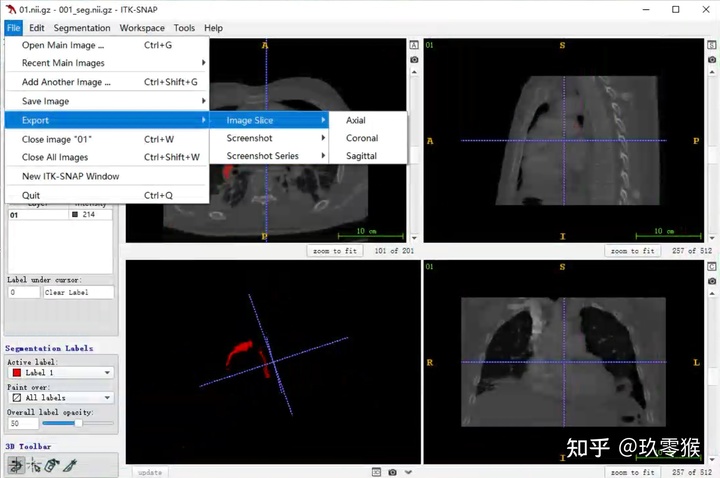

4、导出不同切面的2D图像

4、导出不同切面的2D图像